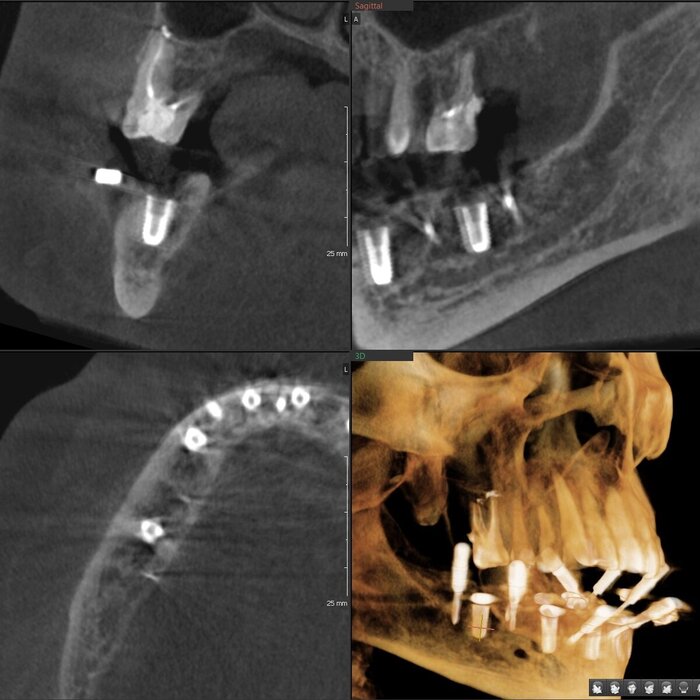

Имплантаты установлены и пациент отправляется на КЛКТ. Каждый раз очень радуется имплантолог, что аппарат находится в клинике. Я тоже рада)

Позиция 4.6

Имплантолог видит, сколько мм можно докрутить безопасно для структур челюсти (нервов, сосудов). Делает дело.

Прошло 6 месяцев.

Сделали КЛКТ:

КЛКТ

Что бы точно никаких вопросов не осталось у доктора, сделали ОПТГ:

ОПТГ

Всё ок, всё прижилось.